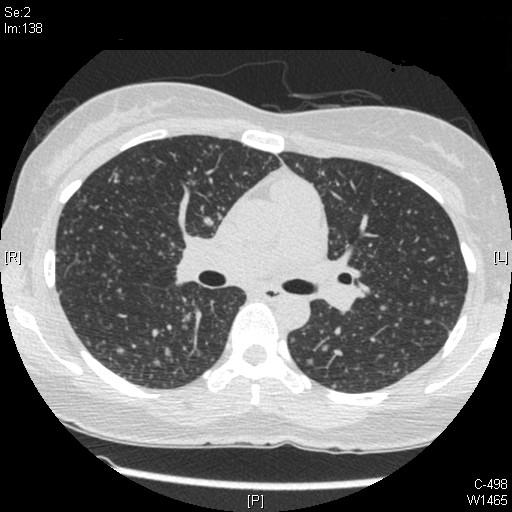

34¼¼ ¿©È¯.

°Ç°¨°ËÁø»ó CXR ÀÌ»ó ¼Ò°ßÀ¸·Î º»¿ø ³»¿ø.

CXR »ó  scattered nodular opacity over the whole lung ¼Ò°ßº¸¿©

Chest CT ÃÔ¿µ ÇÏ¿´À½.

°´´ã°Ë»ç ¹× ±â°üÁö ³»½Ã°æ °Ë»ç»ó AFB smear À½¼º ¼Ò°ß º¸¿´À¸¸ç,

°æÇèÀûÀ¸·Î Tb medication ½ÃÀÛÇÏ¿´À¸³ª °áÇÙ Ä¡·á ÇÑ´Þ ÈÄ¿¡µµ È£Àü ¾ø°í,

Mycobacterial culture ¿¡¼­µµ µ¿Á¤µÇ´Â ±ÕÁÖ ¾ø¾úÀ½.